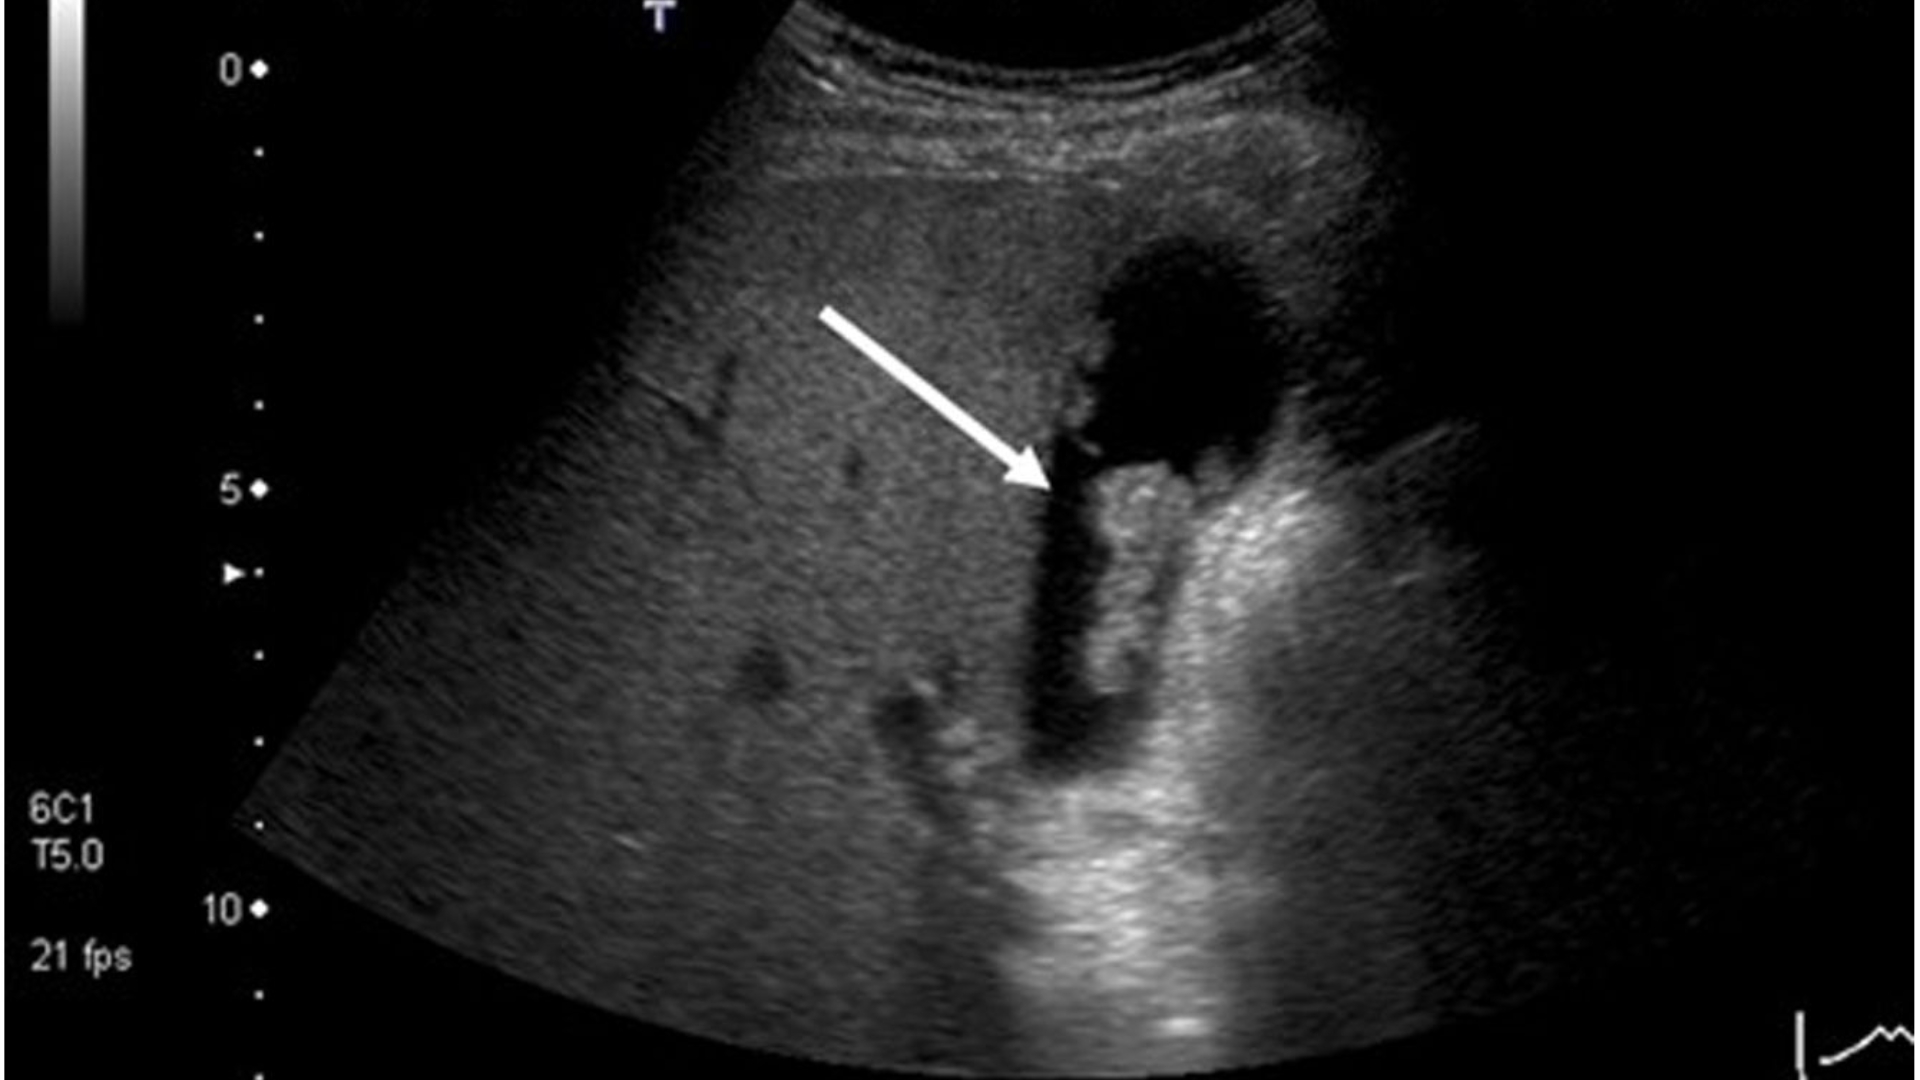

Trên siêu âm, polyp túi mật được mô tả là cấu trúc tăng âm nằm trong lòng túi mật, không tạo bóng lưng và không di động theo thay đổi tư thế, giúp phân biệt với sỏi mật. Polyp cholesterol thường nhỏ (< 10 mm), nhiều polyp, bờ đều, có cuống mảnh, không kèm dày thành túi mật. Trong khi đó, polyp thật có xu hướng đơn độc, kích thước lớn hơn, bờ không đều, và có thể gắn rộng vào thành túi mật.

Một số dấu hiệu nghi ngờ ác tính trên siêu âm bao gồm: Kích thước > 10 mm, phát triển nhanh, mất cuống, cấu trúc không đồng nhất, và kèm theo dấu hiệu dày thành bất thường. Tuy nhiên, phân biệt chính xác bằng siêu âm thông thường vẫn còn nhiều hạn chế, đặc biệt với tổn thương nhỏ hoặc ở vị trí khó quan sát.